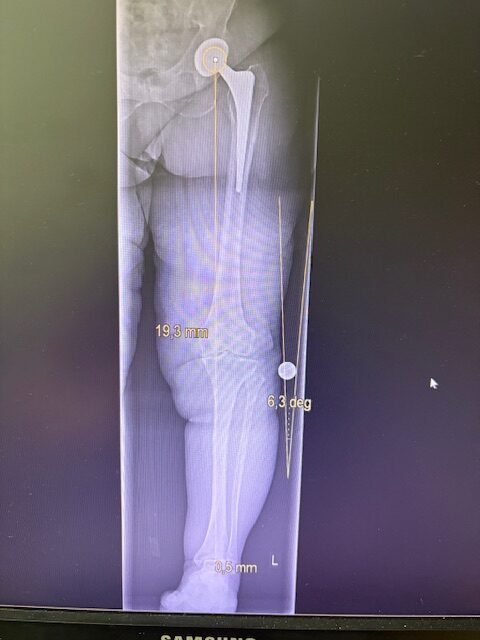

Ο προεγχειρητικός ψηφιακός σχεδιασμός

Πραγματοποιήθηκε σε ειδική ακτινογραφία ολόκληρων των δύο κάτω άκρων. Σε αυτό το ψηφιακό μοντέλο σχεδιάστηκε με ακρίβεια το είδος, το μέγεθος και η ακριβής θέση των προθέσεων, με βάση τα ανατομικά χαρακτηριστικά της ασθενούς.

Ο ψηφιακός σχεδιασμός επιτρέπει απόλυτη εφαρμογή των μοσχευμάτων, ελαχιστοποιώντας τα περιθώρια απόκλισης και εξασφαλίζοντας άριστη ευθυγράμμιση και κινηματική ισορροπία του γόνατος.